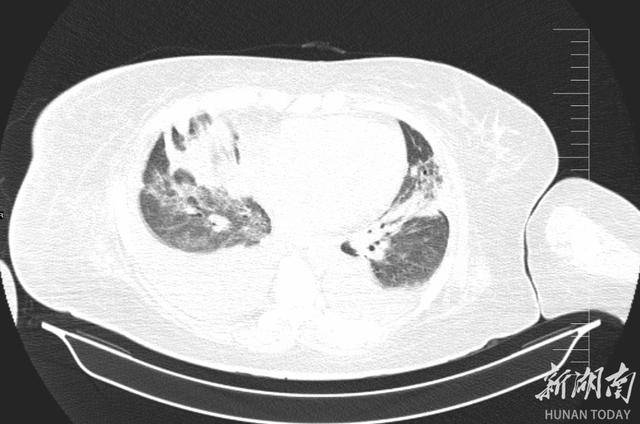

2025 年 12 月 24 日,李阿姨被紧急送入郴州市宜章县人民医院 ICU,她高烧不退、呼吸困难,CT片子上双肺几乎全白了 —— 这是重症肺炎最凶险的信号之一。更麻烦的是,她本身还有肝硬化腹水、十二指肠溃疡大出血等一堆老毛病,所有问题撞在一起,性命危在旦夕。面对如此凶险的病情,救治刻不容缓,ICU 团队火速完成检查并召集多学科会诊,病因被精准锁定:鹦鹉热衣原体感染。

肺部CT可见,重症肺炎较之前大部分被吸收